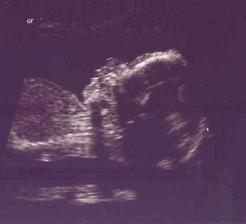

10.6.2010 velký UTZ v 32tt ... vše v pořádku, dle biometrie odpovídá 30+6, bohužel ultrazvuk trval jen asi 10 min., protože se mi udělalo zle z toho vedra a ležení na zádech, tak jsme museli prohlídku urychlit ... pan doktor nám potvrdil pohlaví - bude to chlapeček ... tentokrát jsem to viděla i já 🙂)) ... má 1659g, já navíc 9kg 🙂) ... je hlavičkou dolů, takže už se snad neobrátí 🙂)